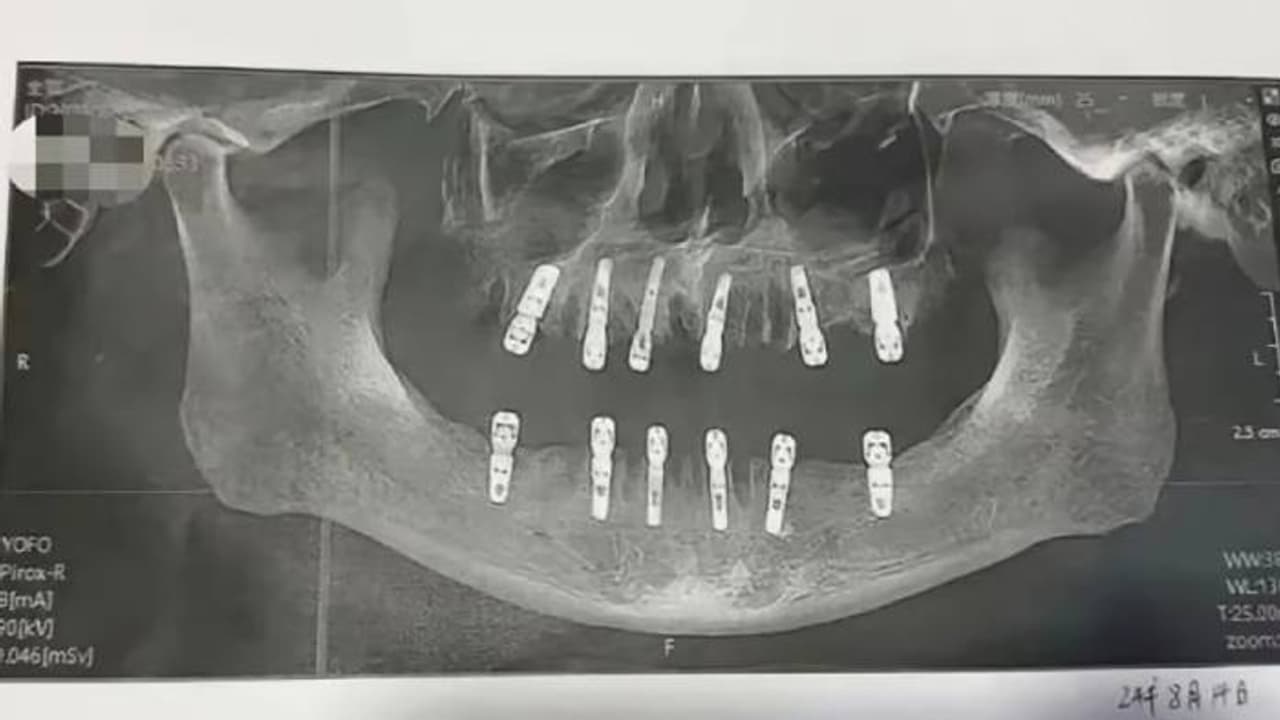

പലതരത്തിലുള്ള മരണങ്ങൾ ഓരോ ദിവസവും നമ്മുടെ ചുറ്റുപാടുകളിൽ നിന്നും റിപ്പോർട്ട് ചെയ്യപ്പെടാറുണ്ട്. എന്നാൽ, കഴിഞ്ഞ ദിവസം ചൈനയിൽ നിന്നും റിപ്പോർട്ട് ചെയ്യപ്പെട്ട ഒരു മരണം അക്ഷരാർത്ഥത്തിൽ ഞെട്ടിക്കുന്നതാണ്. സൗത്ത് ചൈന മോണിംഗ് പോസ്റ്റ് റിപ്പോർട്ട് ചെയ്യുന്നതനുസരിച്ച് ഒരു ദിവസം തന്നെ 23 പല്ലുകൾ പറിച്ചെടുക്കുകയും 12 പുതിയ വെപ്പുപല്ലുകൾ വെക്കുകയും ചെയ്ത ദന്ത ചികിത്സയ്ക്ക് വിധേയനായ വ്യക്തി 13 ദിവസങ്ങൾക്ക് ശേഷം മരണപ്പെട്ടു. മരണപ്പെട്ട വ്യക്തിയുടെ മകൾ സാമൂഹികമാധ്യമങ്ങളിലൂടെ തന്റെ പിതാവിന്റെ മരണത്തെക്കുറിച്ച് പങ്കുവെച്ചപ്പോഴാണ് ഇക്കാര്യങ്ങൾ പുറത്തുവന്നത്.

ഹുവാങ് ഒപ്പിട്ട സമ്മതപത്രം അനുസരിച്ച്, ഒരൊറ്റ ദിവസം തന്നെയാണ് ഇദ്ദേഹത്തിൻറെ 23 പല്ലുകൾ പറിക്കുകയും പുതിയതായി 12 പല്ലുകൾ വെച്ച് നൽകുകയും ചെയ്തത്. യുവാൻ എന്ന ശസ്ത്രക്രിയാ വിദഗ്ധൻ ആണ് തൻറെ പിതാവിൻറെ ശസ്ത്രക്രിയയ്ക്ക് നേതൃത്വം നൽകിയത് എന്നാണ് ഷൂ പറയുന്നത്. ചികിത്സയ്ക്ക് ശേഷം, ഹുവാങിന് അതികഠിനമായ വേദന അനുഭവപ്പെട്ടിരുന്നു. ഒടുവിൽ ആഗസ്റ്റ് 28 ന് ഹൃദയസ്തംഭനം ഉണ്ടായതോടെ അദ്ദേഹം മരണപ്പെടുകയായിരുന്നു.